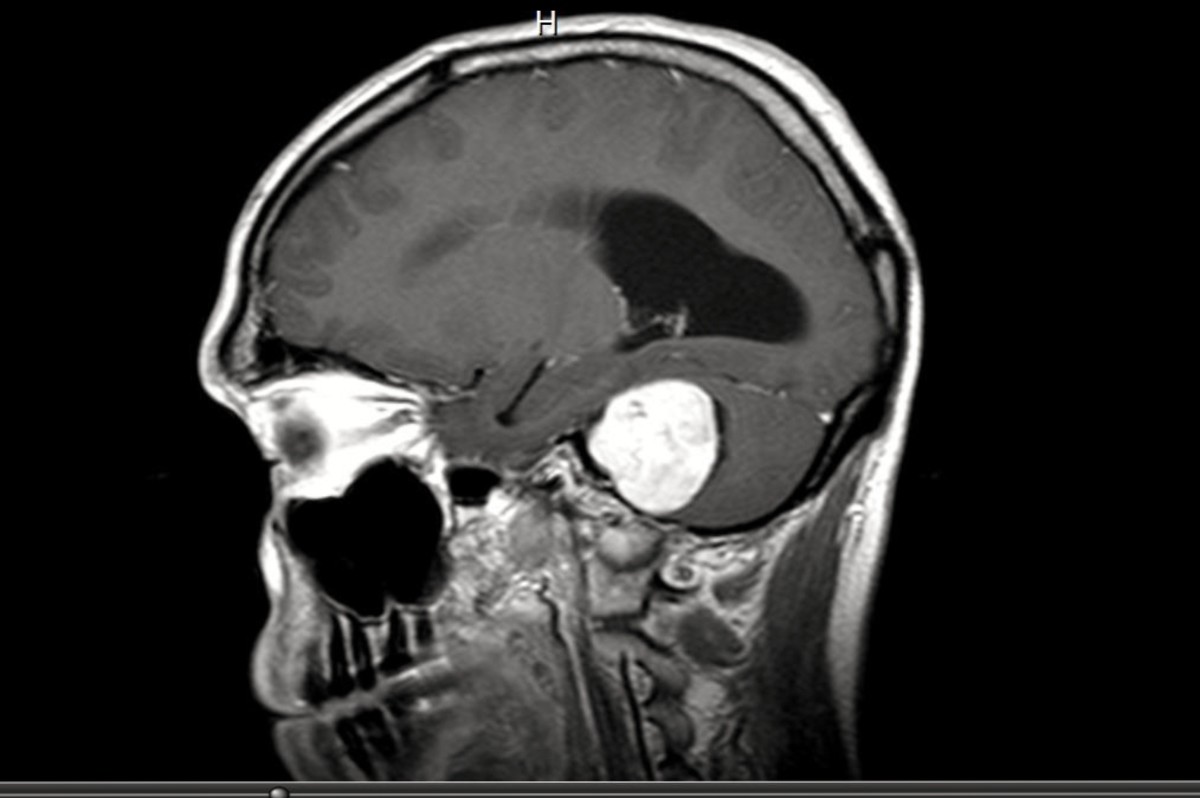

Vestibular Area Of Brain. If disease or injury damages these processing areas, disorders of dizziness or balance can result. Treatment depends on the underlying cause and can include medicine, rehabilitation, and lifestyle changes.

The vestibular system is an essential function of the body that helps humans maintain postural balance and spatial orientation in response to changes in the environment. The cerebellum has input and output connections. The vestibular system is centrally located in the inner ear and is connected to the brain through neural pathways.

Talk to your healthcare provider if you have symptoms of vertigo, dizziness, or hearing changes. Acute lesions (patients with middle cerebral artery infarctions) of this area caused contraversive tilts of perceived. The vestibular system is divided into a central and peripheral system.

As A Result, The Vestibular Area Is Located In Both The Pons And The Medulla.